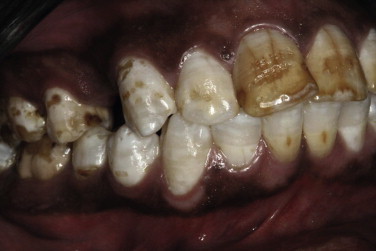

What’s happening here?

Fluorosis from too much fluoride exposure